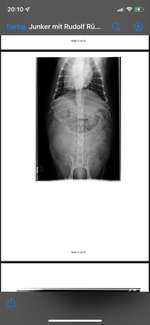

Hallo, mein Hund hat eine Niereninsuffizienz und bekommt 2 x täglich Pronefra. Innereien zu füttern, soll man meines Wissens nach, dabei vermeiden. Da er aufgrund der Nierenproblematik aber eh schon ziemlich mäkelig beim Fressen ist aber gerne Hühnermägen und auch -herz frisst, möchte ich gerne wis ...